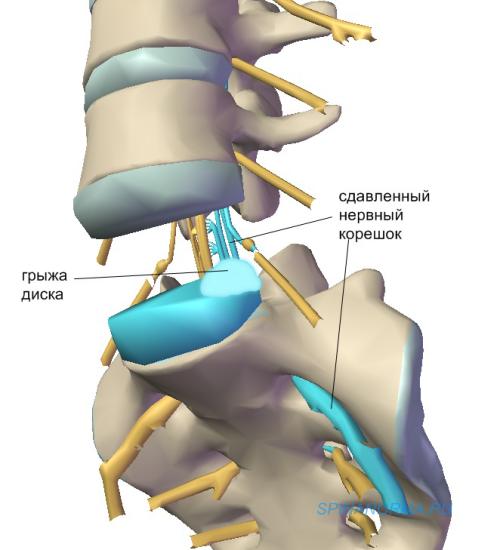

Позвонок Th10: анатомия и фото медицинских иллюстраций